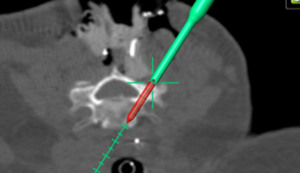

Seit 2017 führen wir unsere Stabilisierungs- und Versteifungsoperationen mit einem intraoperativen CT (s.o. AIRO©, Fa. Brainlab) durch. Diese intraoperative Computertomographie liefert direkt im Operationssaal während des Eingriffs hochauflösende Bilder von der Wirbelsäule. Zusammen mit einer Navigationssoftware wird ein dreidimensionaler Plan der entsprechenden Körperregion erzeugt. Mit Hilfe der Bildgebung können wir die notwendigen OP-Schritte plangerecht umsetzen und z.B. Implantate mit sehr hoher Präzision einsetzen. Gerade bei komplizierten Eingriffen an der Wirbelsäule hilft die neue OP-Technik, Patienten sicher und schonend zu therapieren. Die intraoperative Bildgebung, direkt im OP, erlaubt komplexe Operationen genauer und sicherer durchzuführen und dem Operateur noch während der Operation das Ergebnis zu überprüfen und bei Bedarf zu optimieren. Belastende Folgeoperationen sind so deutlich seltener und die Behandlungsqualität und Sicherheit für Patienten dadurch erheblich verbessert.